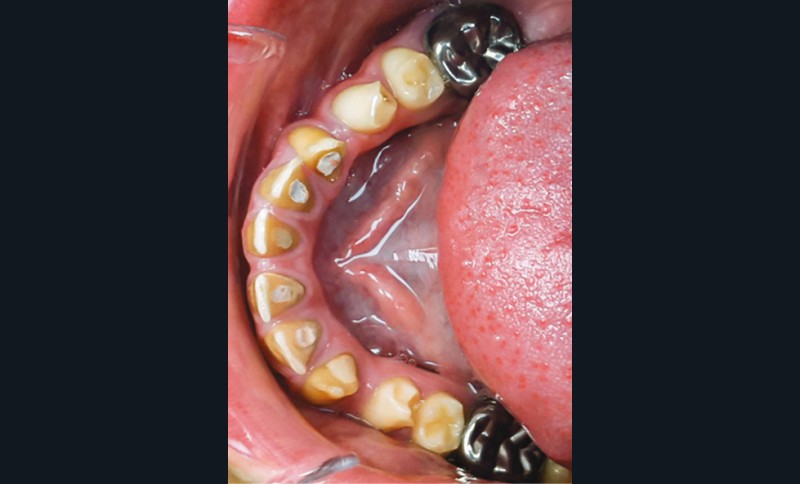

Une patiente âgée de 12 ans a été adressée au cabinet pour « une prise en charge complète sur le long terme » par son praticien traitant. Elle était accompagnée par sa mère. Elle présentait des couronnes transitoires en résine sur le secteur incisivo-canin au maxillaire ainsi que les premières prémolaires, des coiffes pédodontiques métalliques sur les premières molaires, une absence totale d’émail sur l’ensemble de la denture, à l’exclusion des bords libres des incisives mandibulaires (fig. 1 à 3). Le bloc incisivo-canin mandibulaire avait bénéficié de traitements radiculaires (fig. 4). Les incisives maxillaires présentaient des rhizalyses d’une importance significative (fig. 5 et 6). La patiente se plaignait d’hypersensibilités à la mastication et au brossage, la demande esthétique était forte.